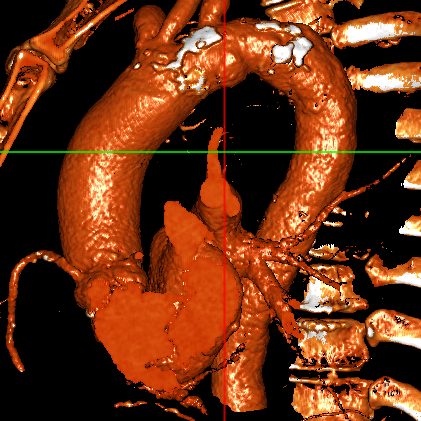

患者为74岁男性,升主动脉增宽,主动脉瓣叶及瓣环明显钙化,中重度狭窄。

武汉协和董念国团队对该病例进行了缜密探讨,该病例为老年男性,主动脉瓣中重度狭窄,术前左室舒张功能减低。患者病例CT和心超数据显示瓣环周长:90.2mm,瓣下4mm流出道周长:97.5mm,窦部空间相对小,单纯无冠瓣瓣叶钙化,三叶瓣。左冠风险较高,缜密分析瓣叶遮盖率>50%,术中可能存在阻挡风险,需要术中球囊扩张时仔细辨认,并准备冠脉保护策略。综合评估考虑右股动脉更适宜为主入路。经过团队严谨的评估及充分的讨论,决定先行25mm球囊预扩并进一步确认冠脉风险,并准备TAV29和TAV32规格的ProStyle预装式可回收TAVR系统。

腹主-股动脉入路

主动脉弓降入路